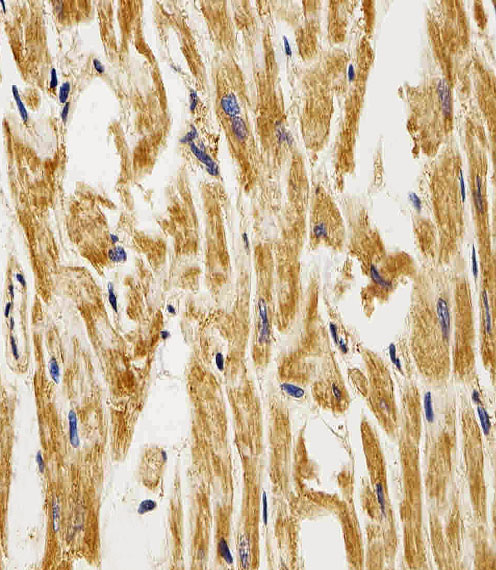

Facts about Fatty acid-binding protein, heart.

| Gene Name: | FABP3 |

FABP11; FABP3; fatty acid binding protein 11; fatty acid binding protein 3, muscle and heart (mammary-derived growthinhibitor); Fatty acid-binding protein 3; Fatty acid-binding protein 3, muscle; fatty acid-binding protein, heart; Heart-type fatty acid-binding protein; HFABP; H-FABP; H-FABPM-FABP; Mammary-derived growth inhibitor; MDGI; Muscle fatty acid-binding protein; O-FABP